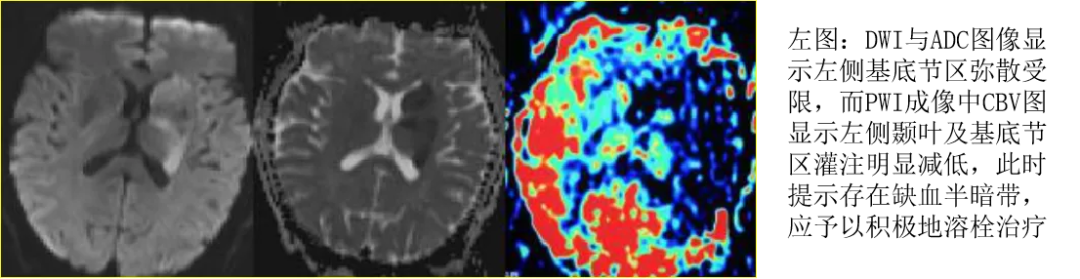

二十一、DWI与PWI联合应用对临床治疗方案选择的指导意义

DWI在早期可显示梗死灶的范围,此范围为我们通常所认为的梗死核心区,PWI能评价缺血区域的血流灌注情况,二者所显示所显示的范围大小具体可分为以下几种情况:

二十二、DWI与PWI联合应用对临床治疗方案选择的指导意义

二十三、WI与PWI联合应用对临床治疗方案选择的指导意义

上图所示:右侧额、顶叶大片梗死灶,DWI上弥散受限区域与PWI成像中的CBV、MTT图灌注异常区域一致,提示不存在缺血半暗带,不建议溶栓治疗。